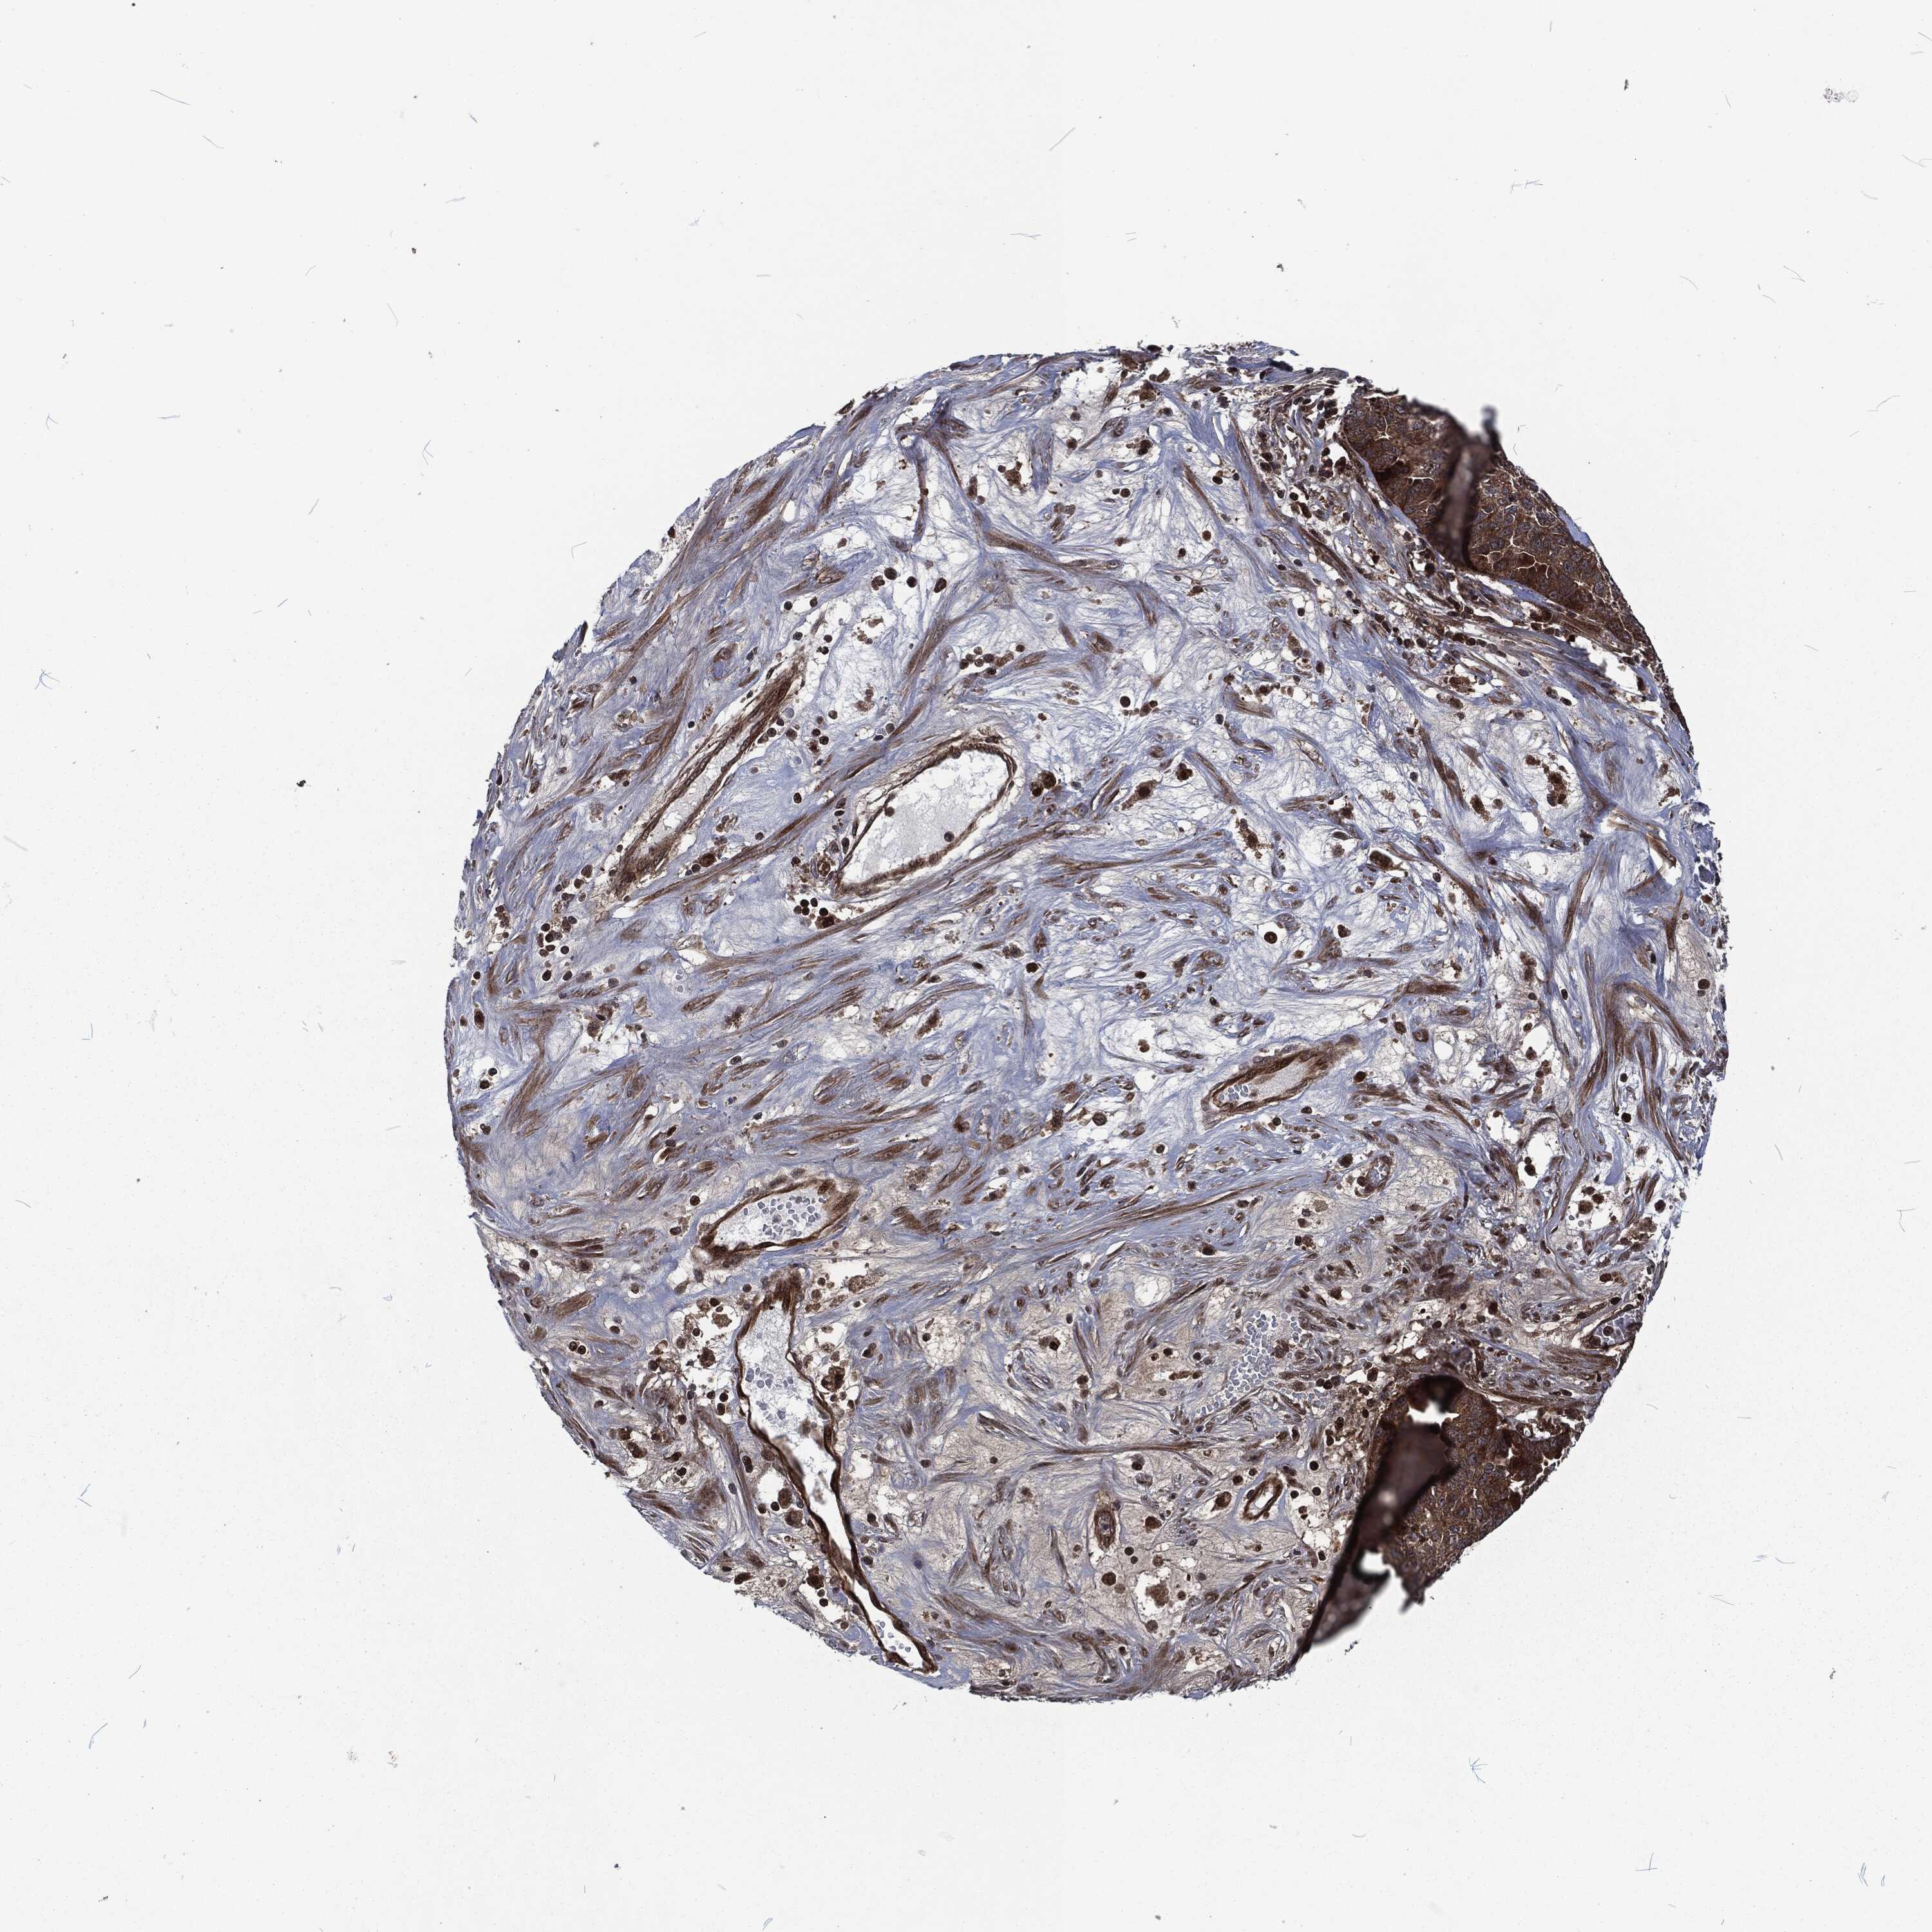

OVARIAN CANCER - Protein expressioni

A mouse-over function shows sample information and annotation data. Click on an image to view it in a full screen mode. Samples can be filtered based on level of antibody staining by selecting one or several of the following categories: high, medium, low and not detected. The assay and annotation is described here.

Note that samples used for immunohistochemistry by the Human Protein Atlas do not correspond to samples in the TCGA dataset.

Antibody stainingi

Antibody staining in the annotated cell types in the current human tissue is reported as not detected, low, medium, or high, based on conventional immunohistochemistry profiling in selected tissues. This score is based on the combination of the staining intensity and fraction of stained cells.

Each image is clickable and will lead to virtual microscopy that enables deeper exploration of all samples and also displays staining intensity scores, fraction scores and subcellular localization as well as patient and tissue information for each sample.

Antibody HPA041430

Antibody HPA062191

Cystadenocarcinoma, serous, NOS

Carcinoma, endometroid

Cystadenocarcinoma, mucinous, NOS

Carcinoma, NOS